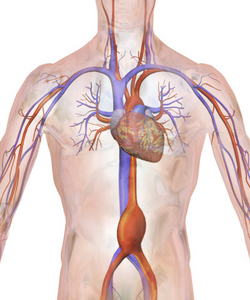

Illustration depicting location of abdominal aneurysm

Abdominal aortic aneurysm involves a regional dilation of the aorta and is diagnosed using ultrasonography, computed tomography, or magnetic resonance imaging. A segment of the aorta that is found to be greater than 50% larger than that of a healthy individual of the same sex and age is considered aneurysmal.[9] Abdominal aneurysms are usually asymptomatic but in rare cases can cause lower back pain or lower limb ischemia.